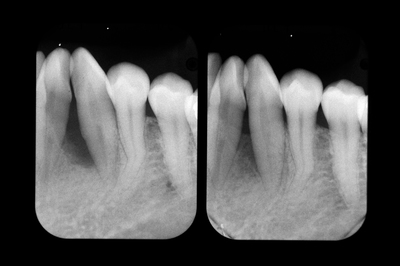

「PD6mm以上は歯周外科」というのがEBMだそうですが、EBMってのもあまりあてにならないことがわかります。そしてこの間の上下前歯部のレントゲン像の変化です。

初診時右上1左下1はすでにに根尖をこえて骨がないようにみえますが、1年半経過し骨が戻ってきました。抜歯の前に当院に来られて本当によかった。